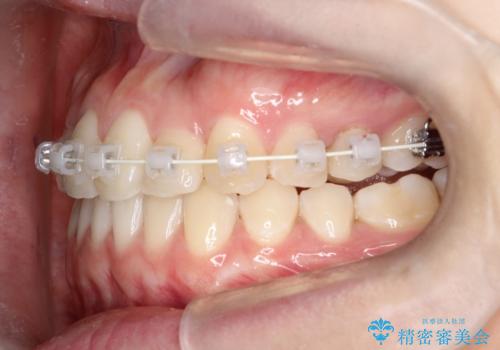

インビザラインとワイヤー矯正の併用で綺麗な歯並びに!

- インビザライン、ワイヤー矯正

- 前歯のガタツキが気になるとのことで来院されました。

ワイヤー矯正とインビザライン矯正を併用することによって、治療期間の短縮と、より良い仕上がりを目指す治療を選択することとしました。

インビザライン(アライナー)矯正とワイヤー矯正のそれぞれの利点を生かした治療を行い、綺麗な歯並びになりました。